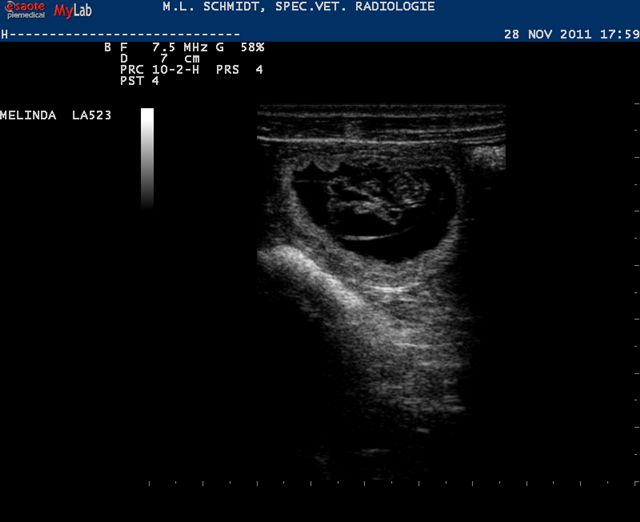

Op deze flipperkast was het vervolgens allemaal prima te zien. “Het zijn er veel” was de eerste opmerking van Chantal de dierenarts. “Tja, wat is veel?” was mijn wedervraag. De schatting bleef steken bij 6 tot 7; dat is eigenlijk precies de gemiddelde nestgrootte van een whippet. Uiteindelijk blijft het een verrassing; er kunnen nog vruchtjes afsterven in de komende tijd, maar er kunnen er vandaag ook nog wel ongezien zijn gebleven.

Ik vond wel, dat de kwaliteit van de echo iets minder was dan destijds met Jewel; het komt waarschijnlijk doordat er omhoog geduwd moet worden met de sensor. De automatische reactie van Hinde was om haar rug omhoog te trekken, die moesten we dus wat omlaag duwen, al met al denk ik dat het contact daardoor iets minder goed zal zijn geweest.

Maar goed, de frutseltjes waren toch wel goed te onderscheiden. De afmeting van de vruchtblaas waar ze inzitten werd ook nog gemeten: 3,3 centimer; de maat van een walnoot ongeveer.